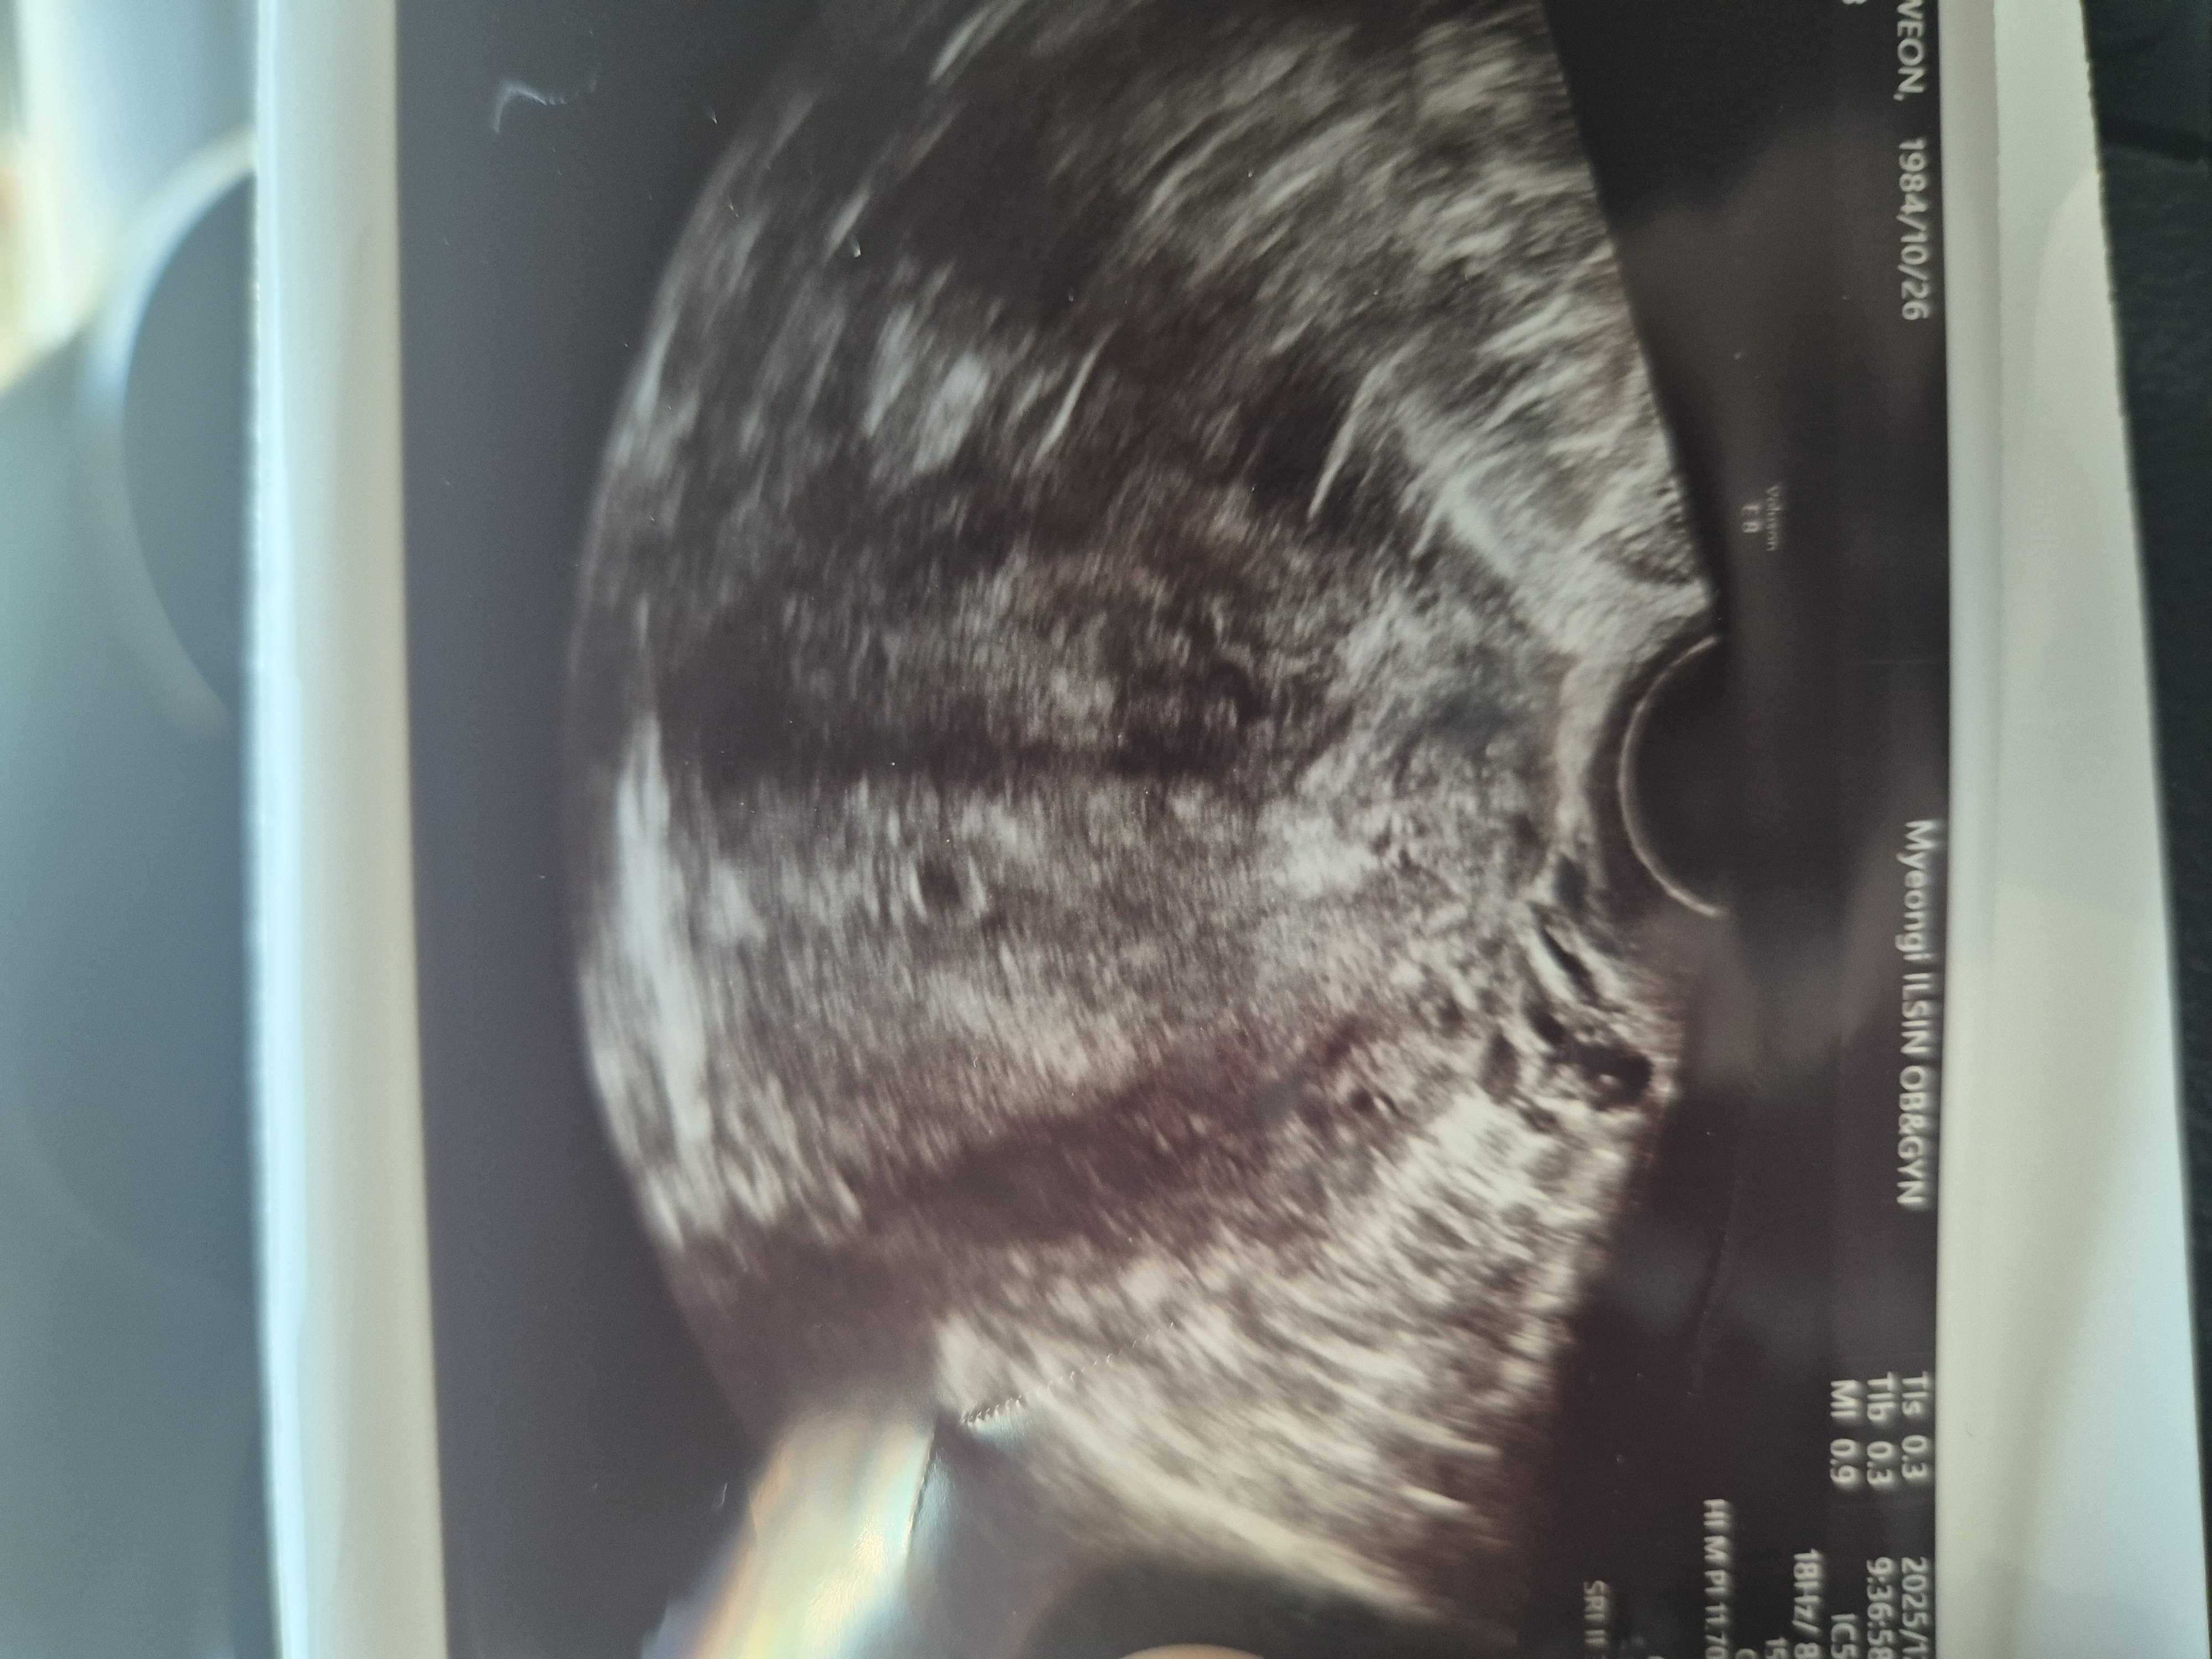

7주 시작인데,,

오늘 병원가서 아기집 확인하고 왓는데,,아기집이 좀 작다고 해서요.. 괜찮을까요?

자연임신이고 생리주기가 길면 모르겠지만 그게 아니라면 7주차에는 최소 난황이나 심장 깜빡임은 보여야해요ㅠㅠ